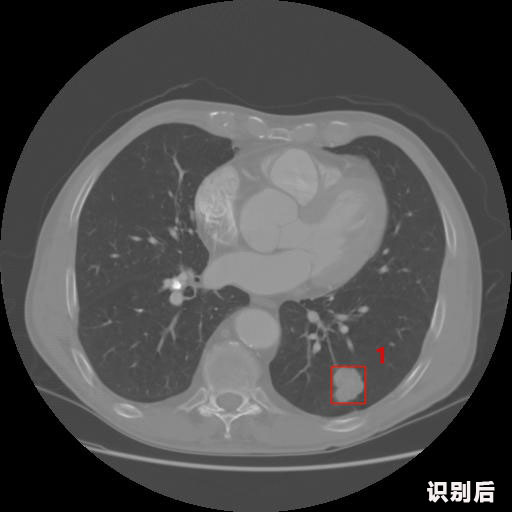

英特健康AI深度學習醫(yī)療圖像識別系統(tǒng)案例_胸部CT

1.發(fā)現肺結節(jié)的可能性為95.56%---位于框指數位置:[331.70554 366.13406 365.21707 403.96234]